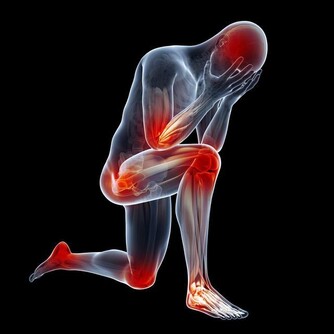

皮膚瘙癢,為什麼會越抓越癢?

撓抓皮膚,使得嬌嫩的皮膚表層被剝落脫掉,真皮層裸露,被細菌和真菌感染,產生炎症反應,因此越抓越癢。又因太用力,皮膚被抓破了真皮層,導致感覺又痛又癢,但是覺得還不解癢。如此抓幾次之後,更是引起表皮剝脫,進一步加重皮膚乾燥的問題,瘙癢感繼續加重,甚至嚴重到身體有點熱度時,身體就開始發癢。

皮膚瘙癢其實是皮膚的一種主觀症狀,主要表現為局部或全身性的瘙癢,不一定伴有皮膚症狀,但由於許多人會忍不住“撓一撓”,大多數瘙癢的患者皮膚上可見抓痕。

過度搔抓會破壞皮膚的完整性,從而使瘙癢的情況加重,導致“越撓越癢,越癢越撓”的惡性循環,甚至引起繼發性的皮損和感染:

- 皮膚損傷,如色素沉著、瘢痕等;

- 皮膚感染,如毛囊炎、淋巴結炎等。